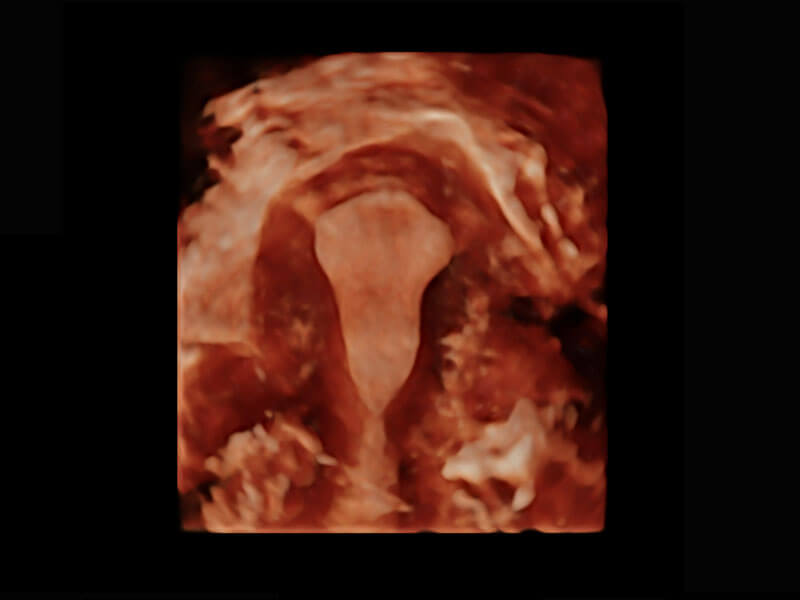

腔內(nèi)三維-宮內(nèi)節(jié)育器

腔內(nèi)三維-光影成像